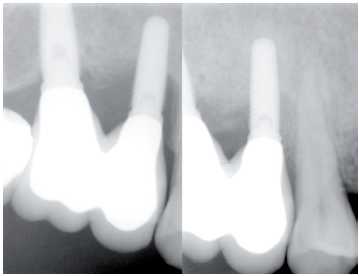

— Exploración radiológica al cumplirse un año

• Rx. Periapicales en aquellos implantes comprometidos: espiras

expuestas, movilidad, sangrado, etc., con técnica de

paralelización.Esta técnica nos asegura que la

proyección es la misma y evita distorsiones que pueden

llevar al clínico a una lectura distinta a la situación

real de pérdida ósea o desajuste de la conexión

del implante con la prótesis (Figura 7).